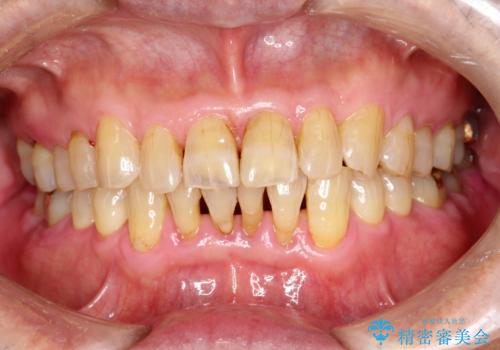

- 2カ月ごとにメンテナンスにいらしている方です。染め出しをしての歯磨きチェックとPMTC30分コースを行いました。

口腔内にはたくさんの細菌がいるため、ヌルヌルとしたプラーク(歯垢)が自然に歯の表面に付きます。

このプラーク(歯垢)にはたくさんの細菌が潜んでおり、虫歯や歯周病・口臭などの最大の原因です。そのため、毎日の歯磨きでプラーク(歯垢)をキレイに取り除くことが、健康な歯を保つためには欠かせません。